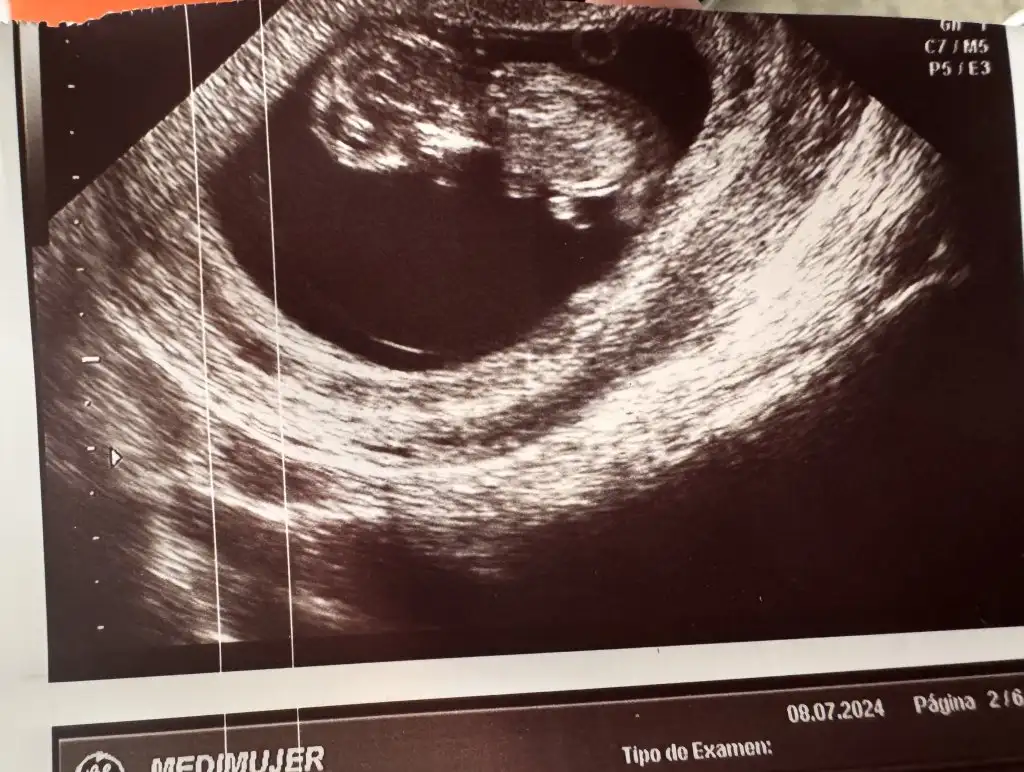

Merhabalar çok merak ediyorum tahmin edebilir misiniz? 🫣

Eklentiler

• F6F28436-785A-4088-A861-0E27EC90DF8D.webp

F6F28436-785A-4088-A861-0E27EC90DF8D.webp

23 KB · Görüntüleme: 53